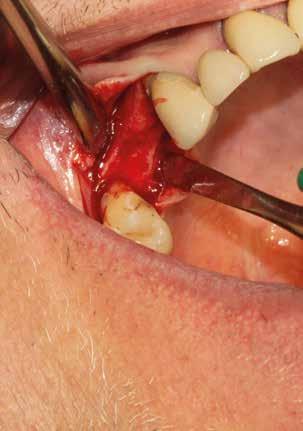

Esempio chirurgico di accesso tra 2 elementi dentari con conformazione della cresta alveolare ampia. Incisione del lembo in cre sta senza scarichi laterali con sollevamento di 2 lembi, palatale e vestibolare; si può notare come quest’ultimo non si estenda oltre

Estrazione di 3 elementi dentari complicata da frattura coronale di 2.4 e presenza di 2 corone protesiche unite su denti pluriradicolati. L’approccio deve prevedere la rimozione delle corone protesiche e la separazione delle radici, semplificando le manovre di estrazione e consentendo di risparmiare i tessuti molli pericoronali e prevenire la frattura

Il rispetto dei tessuti molli consente di ridurre i tempi di guarigione, sebbene a siti più ampi corrisponda un tempo di ripristino o maggiore. Il mantenimento delle corticali vestibolari, palatine e l’assenza di alveolite post-estrattiva riducono l’atrofia ossea.